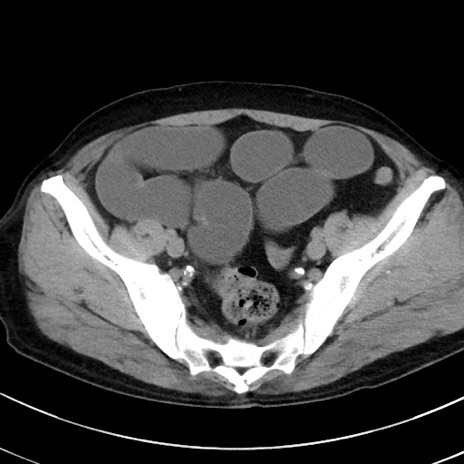

冠状断像

【症例】70歳代 男性

【主訴】腹痛・嘔吐

【現病歴】昨晩より、嘔吐・腹痛あり。今朝になっても嘔吐あり。来院。

【既往歴】心臓バイパス手術、開腹胆摘、腸閉塞

【身体所見】BP 107/71mmHg、HR 116/min、腹部:平坦、軟、下腹部に軽度圧痛あり。反跳痛なし。

【データ】WBC 15100、CRP 0.32